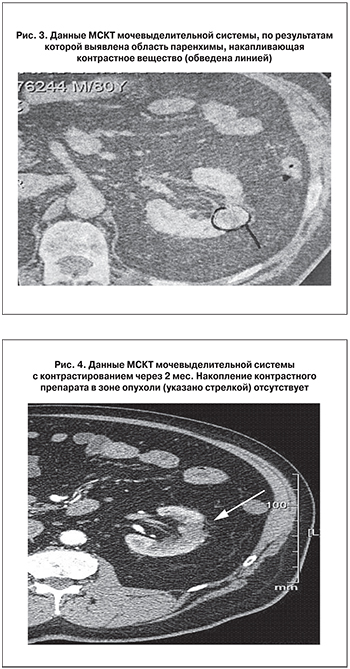

П а ц и е н т В. 1935 г. рождения с 1985 г. страдает хроническим рецидивирующим простатитом, в 1995 г. поставлен диагноз доброкачественной гиперплазии предстательной железы (ДГПЖ). В 1997 г. пациенту была выполнена чреспузырная аденомэктомия. В 2004 г. был выявлен рецидив ДГПЖ объемом 80 см3 при наличии остаточной мочи объемом 100 см3 и уровня общего простатспецифического антигена ПСА 4,0 нг/мл, в связи с чем была выполнена трансуретральная резекция (ТУР). Послеоперационный период протекал без осложнений, по результатам гистологического исследования – ДГПЖ. В 2010 г. при ультразвуковом сканировании в левой почке определена киста с прилегающим участком паренхимы, подозрительным на объемное образование (рис. 1). При МСКТ мочевыделительной системы с болюсным введением контрастного препарата в левой почке были выявлены субкапсулярная киста диаметром 20 мм, не накапливающая контрастное вещество и интимно прилегающее к ней объемное образование диаметром 12 мм, накапливающее контраст (рис. 2).

В связи с наличием у пациента сопутствующей патологии (состояние после имплантации ЭКС от 08.2008, гипертоническая болезнь II ст., гипертоническое сердце, эмфизема легких, сахарный диабет 2 типа, стадия компенсации и отказ пациента от радикального лечения) в октябре 2010 г. было принято решение выполнить диагностическую пункцию и ИЛК образования почки под УЗ-контролем.

В ходе операции проведена пункция кисты, при которой получено 13 мл светло-желтой жидкости, и тонкоигольная биопсия (18 G) прилегающего к ней образования почки; материалы отправлены на цитологическое и гистологическое исследования. По результатам интраоперационной цитологической диагностики были обнаружены клетки почечно-клеточного рака. Затем последовательно установлены 4 пункционные иглы в объемное образование, через которые с помощью оптоволоконного проводника выполнена лазерная коагуляция с применением отечественного микросекундного Nd:YAG лазерного хирургического комплекса в режиме: частота 100 Гц, мощность 23 Вт, энергия 384 мДж, время воздействия 2 мин в каждый прокол. Послеоперационный период протекал без сложнений. Гистологическое заключение: светлоклеточный почечно-клеточный рак с ядерной градацией G1.